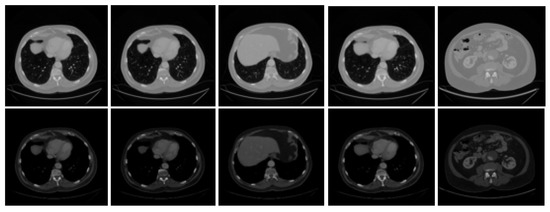

3.2. Preprocessing

Generally, medical imaging datasets have a noisy texture that causes the ROI to fade out. The noise could include any kind of blotches, irregular spots, unwanted objects, and organs. A medical imaging dataset needs to be preprocessed first to make it suitable for further experimentation. This step is mandatory to achieve enhanced images, as raw data is noisy most of the time and cannot be processed further. It is very important to enhance ROIs by eliminating unwanted noise; for this purpose, various researchers have proposed multiple techniques. Mostly, contrast enhancement is used to improve the image quality. This is done using windowed Hounsfield unit values in the range [−100, 400], which results in an enhanced image without any kind of noisy blotches, irregular spots, organs, and unwanted objects. We have used this preprocessing step over the dataset to enhance the visibility of ROI and achieve a better image quality. This preprocessing technique is also followed by other researchers [27,29]. Figure 2 shows some samples from the 3DIRCADb dataset before and after the enhancement operation was applied.

Figure 2.

Samples of raw and enhanced CT scan images from the 3DIRCADb Dataset.